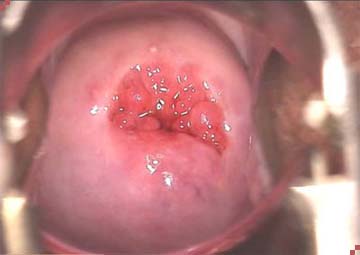

Khi đến phòng khám kiểm tra bằng máy sẽ thấy:

- Lớp biểu mô lẽ ra ở lỗ trong cổ tử cung, nhưng đã lan ra ngoài che phủ một phần cổ tử cung, ở dưới là lớp đệm.

- Có nhiều mạch máu tạo ra hình ảnh một tổn thương có màu đỏ và sần sùi giống như mô hạt.

Quan sát bằng máy sẽ thấy có 2 trường hợp bị viêm lộ tuyến cổ tử cung:

- Lộ tuyến nông là vùng tổn thương có thể xuất hiện trên diện rộng nhưng lớp tế bào liên kết ở bề mặt chưa hết hẳn.

- Lộ tuyến sâu là khi các lớp tế bào đã mất hết, lớp đệm phía dưới lộ hẳn lên bề mặt.

Mức độ viêm lộ tuyến cổ tử cung nặng hay nhẹ được đánh giá thông qua sự tổn thương của tế bào ở mức độ nông hay sâu. Để đánh giá chính xác mức độ tổn thương, cần phải khám và làm xét nghiệm tế bào.

Hình ảnh viêm lộ tuyến cổ tử cung